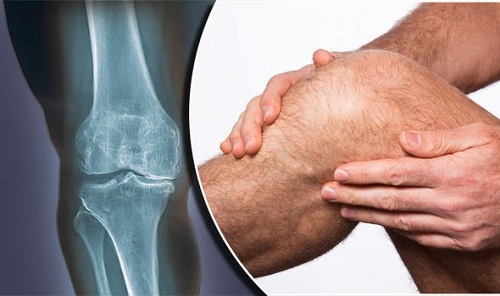

علت زانو درد در جوانی سی تا چهل سالگی

علت زانو درد در جوانی سی تا چهل سالگی علت زانو درد در جوانی سی تا چهل سالگی امروزه زانو درد یکی از عارضه های شایعی است که اکثر افراد آن را تجربه می کنند، با این حال زانو درد در جوانی کمی سوال برانگیز است و ممکن است شما به دنبال دلیل آن باشید. در این مطلب از کلینیک خانه درد قصد داریم تا به بررسی علت زانو درد در جوانی و میان سنین سی تا چهل سالگی بپردازیم.

اگر شما یا عزیزانتان از این درد رنج می برید و به دنبال علت و روش های درمان آن هستید، تا انتها این مطلب همراه ما باشید.